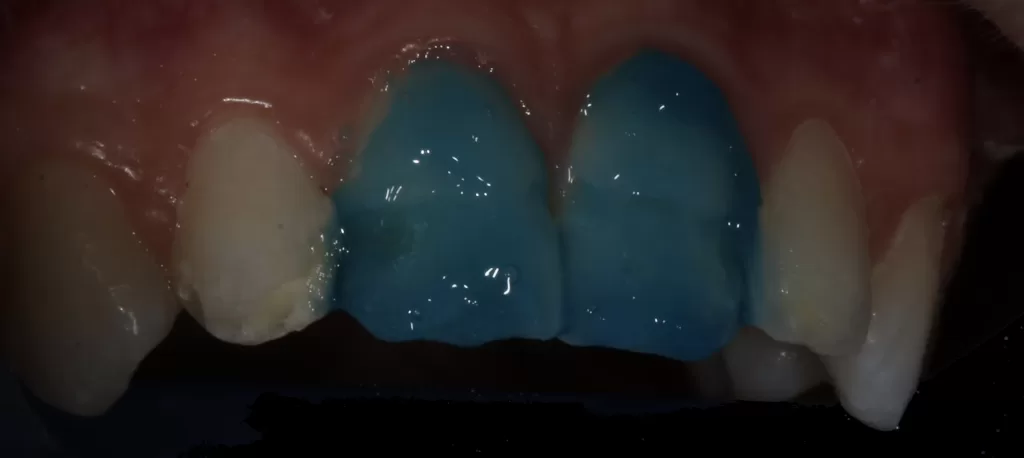

- Preoperative photographs (Fig 1).

- Mock-up of final veneer to assess shade selection and ability to mask discolouration using Uveneer (Ultradent, South Jordan, Utah, United States) template (Fig 2).